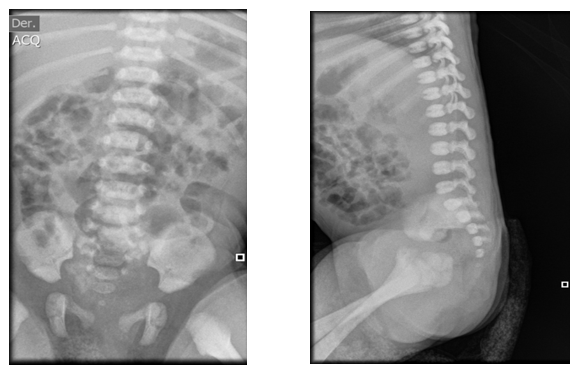

Figure 3 Lumbar spine x-ray technique: AP and lateral projection. Findings: There is no evidence of soft tissue alteration. The lumbar lordosis is preserved and the load-bearing spine is not displaced. The vertebral bodies have normal morphology, height and density according to the patient's age. The intersomatic spaces have normal width. The pedicles, spinous and transverse processes have normal morphology and density. The sacrum and coccyx have a normal anatomical position.